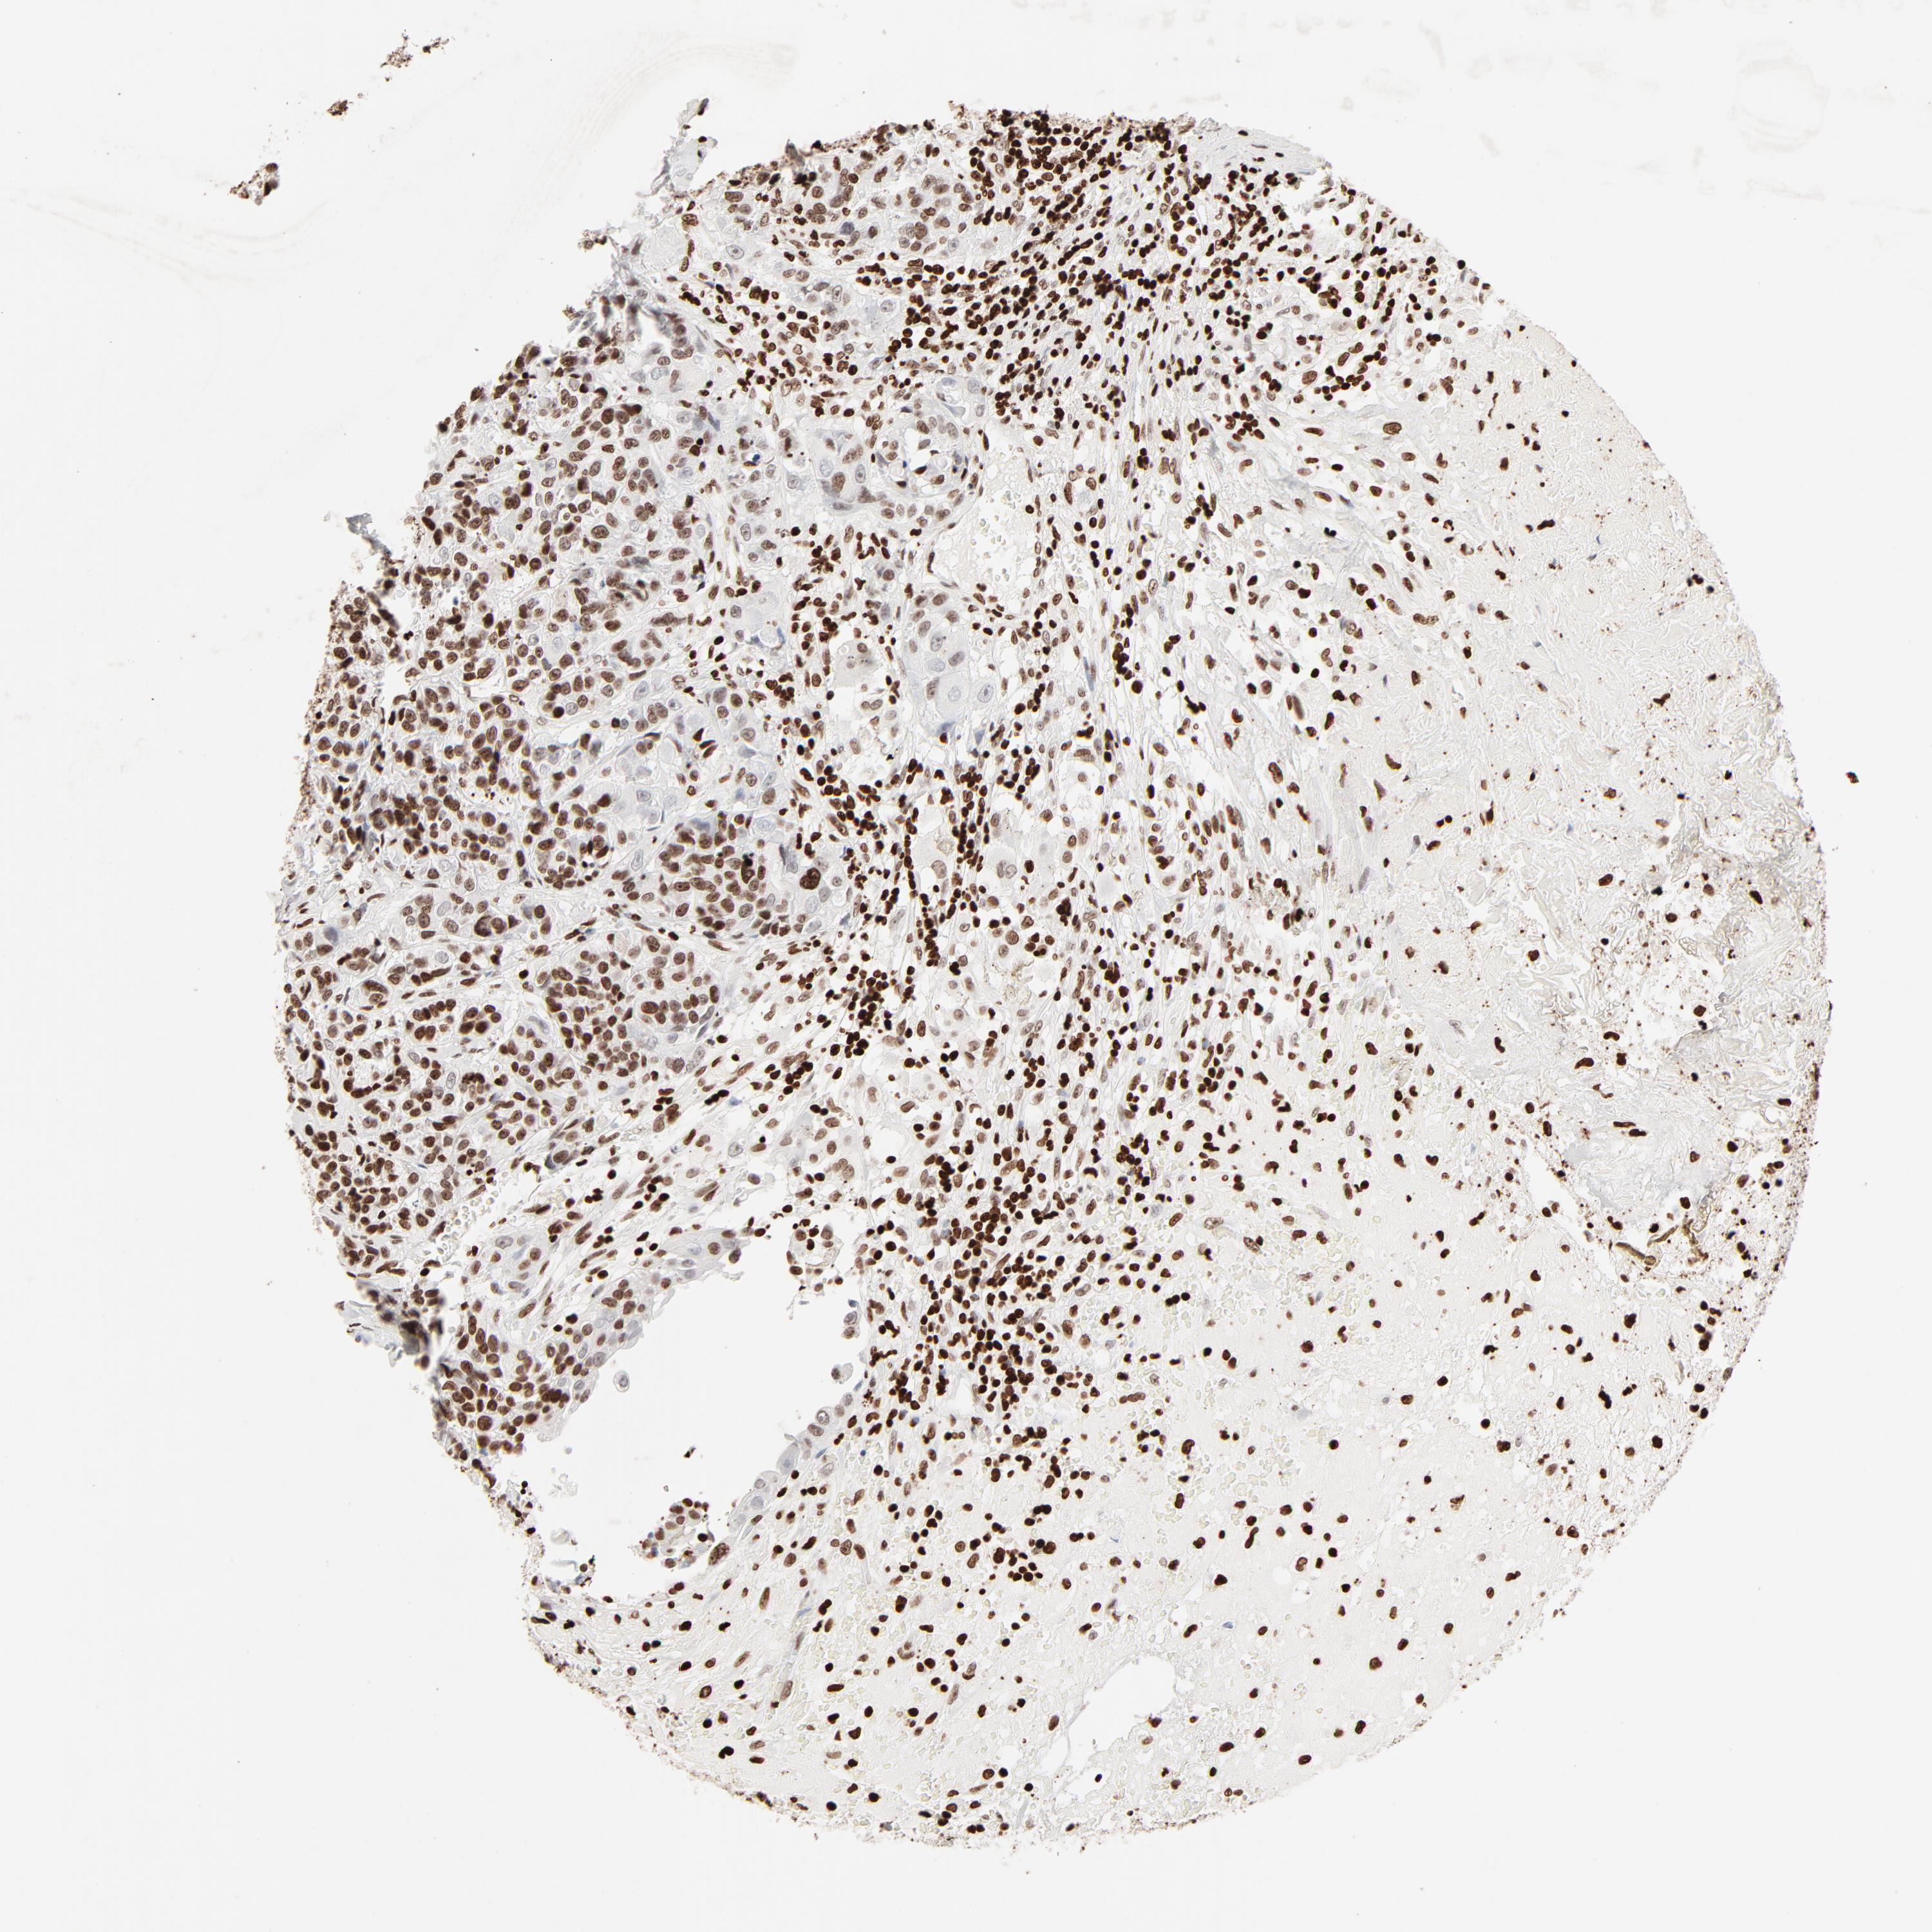

UROTHELIAL CANCER - Protein expressioni

A mouse-over function shows sample information and annotation data. Click on an image to view it in a full screen mode. Samples can be filtered based on level of antibody staining by selecting one or several of the following categories: high, medium, low and not detected. The assay and annotation is described here.

Antibody stainingi

Antibody staining in the annotated cell types in the current human tissue is reported as not detected, low, medium, or high, based on conventional immunohistochemistry profiling in selected tissues. This score is based on the combination of the staining intensity and fraction of stained cells.

Each image is clickable and will lead to virtual microscopy that enables deeper exploration of all samples and also displays staining intensity scores, fraction scores and subcellular localization as well as patient and tissue information for each sample.

Antibody HPA003506

Antibody CAB005873

Urothelial carcinoma, High grade

Urothelial carcinoma, Low grade